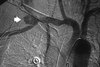

arrow is pointing at what artery?

axillary artery commences at the first rib as a direct continuation of the subclavian artery and becomes the brachial artery at the lower border of the teres major. The arteriogram reveals a nonfilling defect in the third portion of the artery just distal to the subscapular artery. The complex arterial collateral circulation in this region often permits distal perfusion of the extremity despite injury.